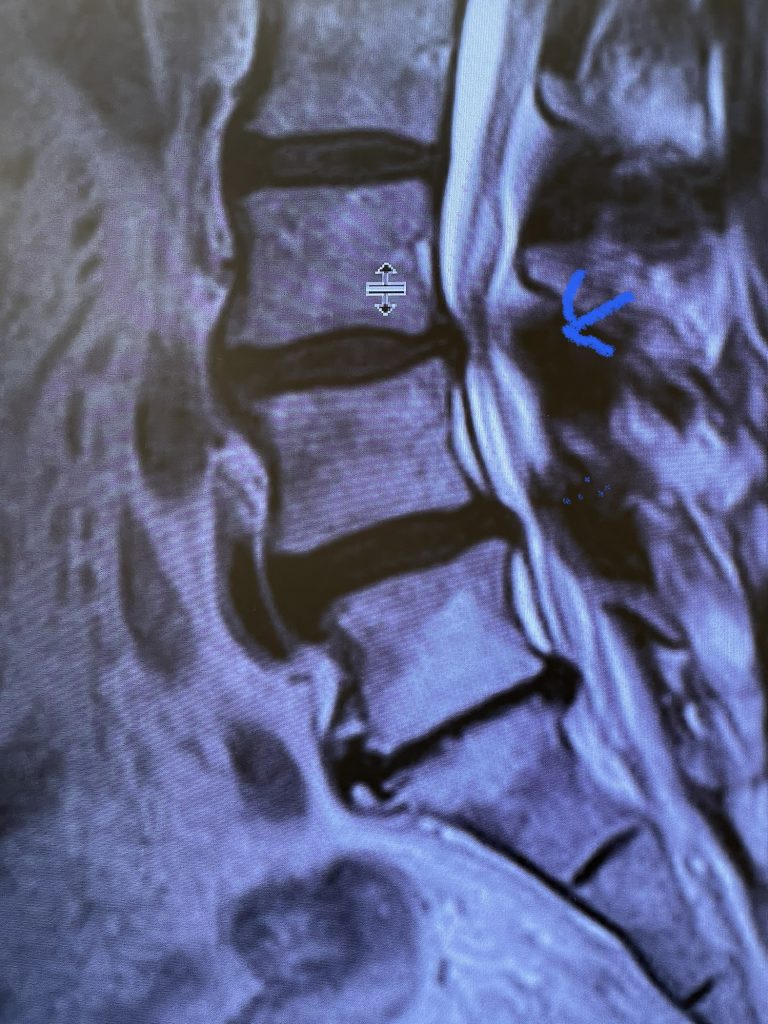

The spinal synovial cyst is one of the most interesting expressions of spinal instability. They emanate from the synovial lining of a degenerated facet joint that […]

People are obsessed with cysts! When you think about it, the body likes to form cysts. Why does this happen? Cysts can form just about anywhere […]